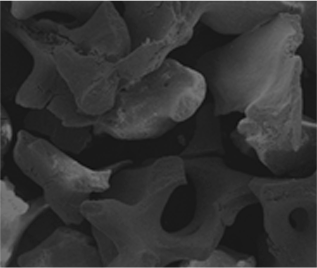

본어스 식립 케이스 9

본어스 식립 케이스 10